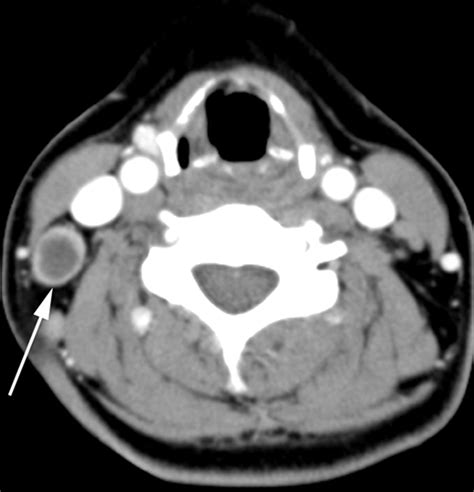

• Imaging Tests: Imaging tests, such as ultrasound, CT scan, or MRI, can help visualize the lymph nodes and detect any abnormalities.